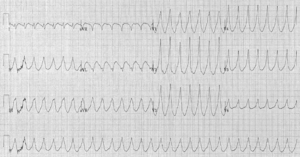

Фибрилляция желудочков

Фибрилляция желудочков является опасным для жизни состоянием, при котором нарушается нормальный ритм сердца. Оно характеризуется хаотичной и некоординированной электрической активностью желудочков сердца, что приводит к их неэффективному сокращению и прекращению нормальной циркуляции крови. Симптомы желудочковой фибрилляции возникают при кардиалгии, потери сознания, остановки дыхания, отсутствия пульса на крупных артериях. Диагностика патологии основана на данных электрокардиограммы, УЗИ сердца, биохимического анализа крови. Лечение проводится незамедлительно с применением дефибриллятора для восстановления физиологического сердечного ритма[10].

Фибрилляцию необходимо отличать от трепетания желудочков, при котором число импульсов не превышает 200—300 ударов за минуту, а все волны имеют одинаковую амплитуду и конфигурацию. Дифференциальную диагностику проводят с другими кардиоваскулярными патологиями: полной блокадой сердца, асистолией, массивной тромбоэмболией лёгочной артерии, тампонадой сердца. При нетипичной клинической картине следует исключить гиповолемический шок, отравление ядами или лекарствами[10].